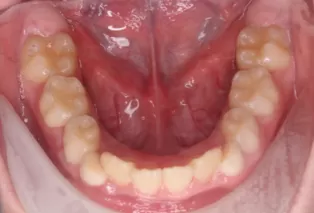

Photos intra-orales après traitement